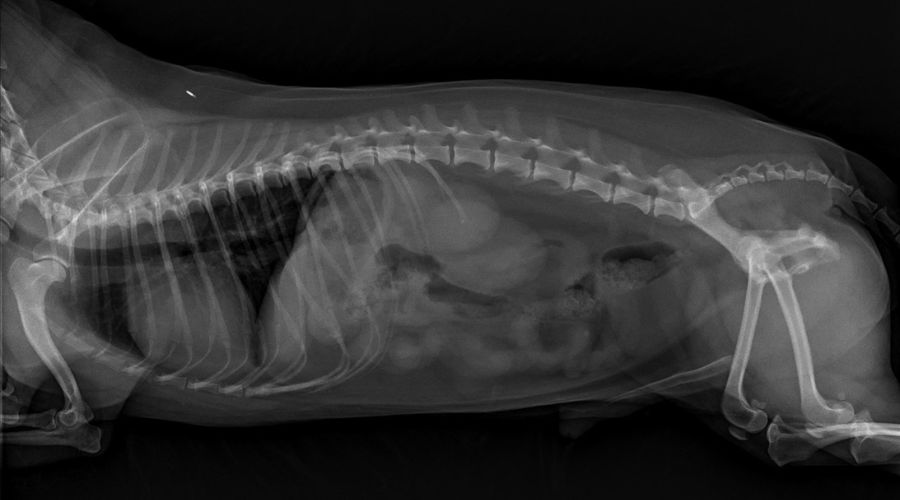

Radiology

We offer routine radiographs (X-rays) for bone and joint disease, renal or bladder stones, chest radiographs for heart disease or pneumonia, and cancer screenings.